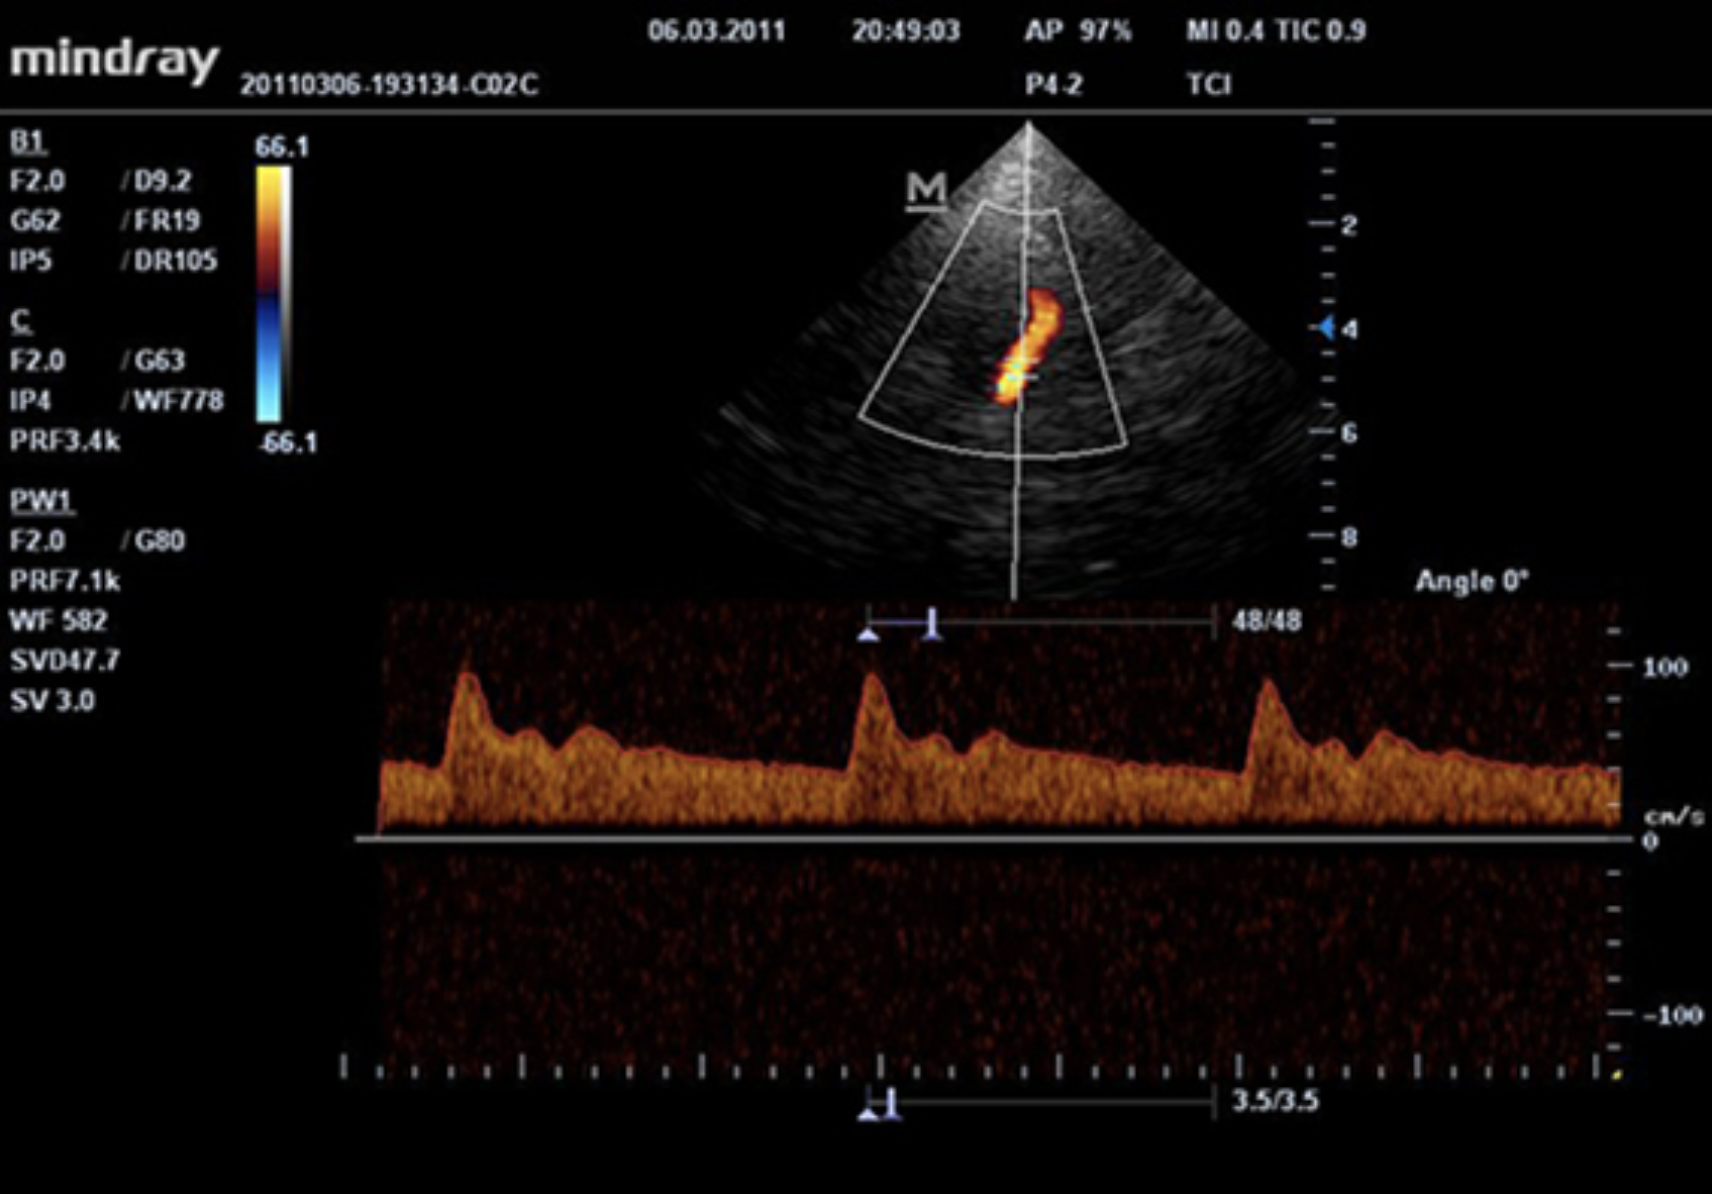

Визуализация средней мозговой артерии в PW режиме с помощью секторного датчика P4-2

Визуализация сердечной мышцы и аортальной регургитации с помощью секторного датчика P4-2S